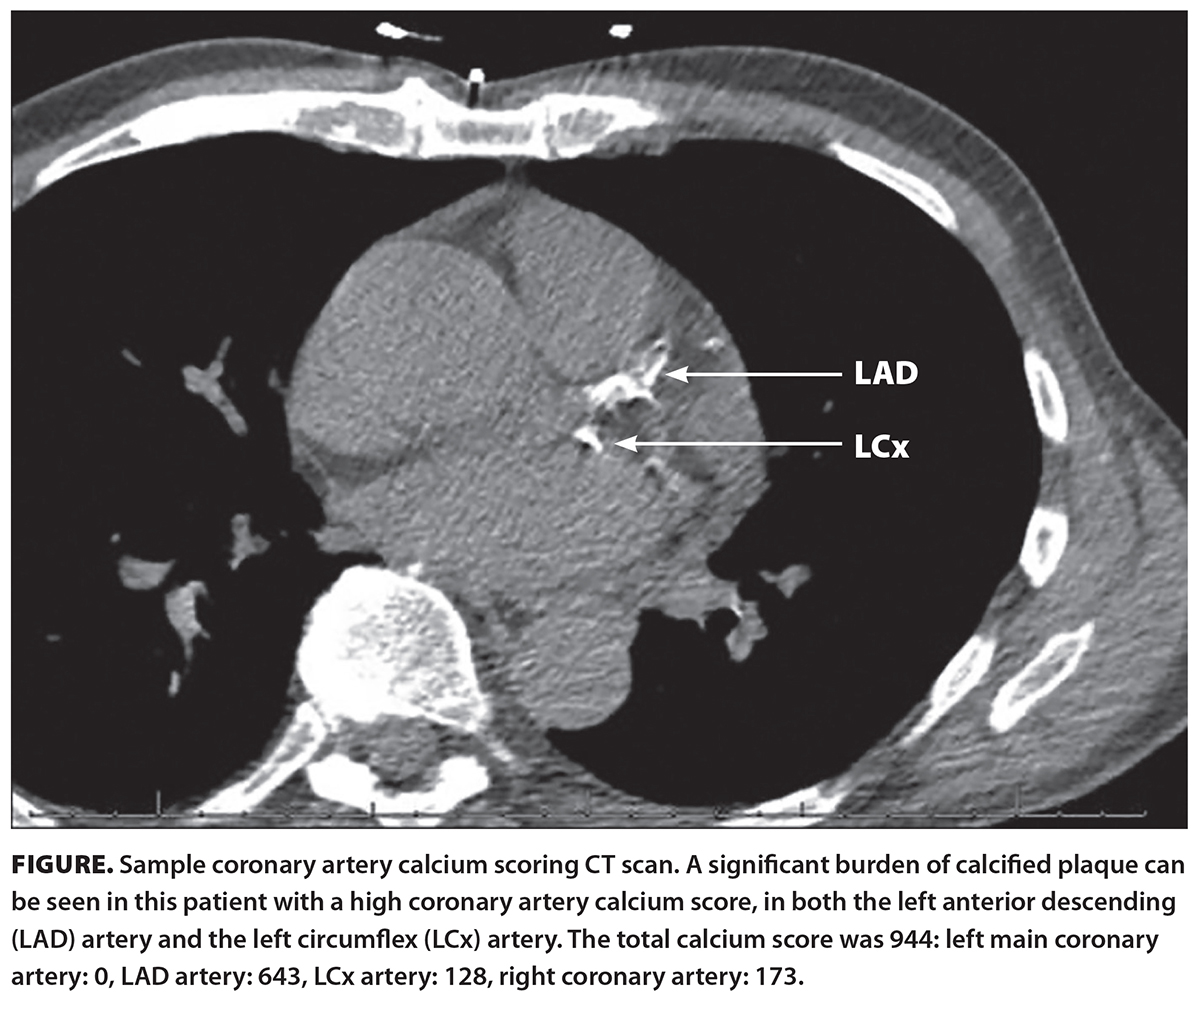

Coronary artery calcium scoring (CACS) is a noninvasive, specialized computed tomography (CT) scan of the heart that is used to assess the presence of calcified plaque in the coronary arteries [Figure]. It is used in evaluating the risk of atherosclerotic cardiovascular disease in asymptomatic patients and offers a direct measure of subclinical atherosclerosis. It requires approximately 10 minutes of patient time in the procedure room. The radiation exposure of the scan does not exceed 1.0 mSv, which is comparable to that of a screening mammography (approximately 0.8 mSv) and lower than the yearly radiation exposure (i.e., natural environmental radiation) of approximately 3.0 mSv. CACS has been incorporated into various guidelines and criteria, where clinically suitable, including those of the Society of Cardiovascular Computed Tomography and the Society of Thoracic Radiology.[4-8] The presence of calcium in the coronary arteries is strong evidence of atherosclerotic plaque.[9]